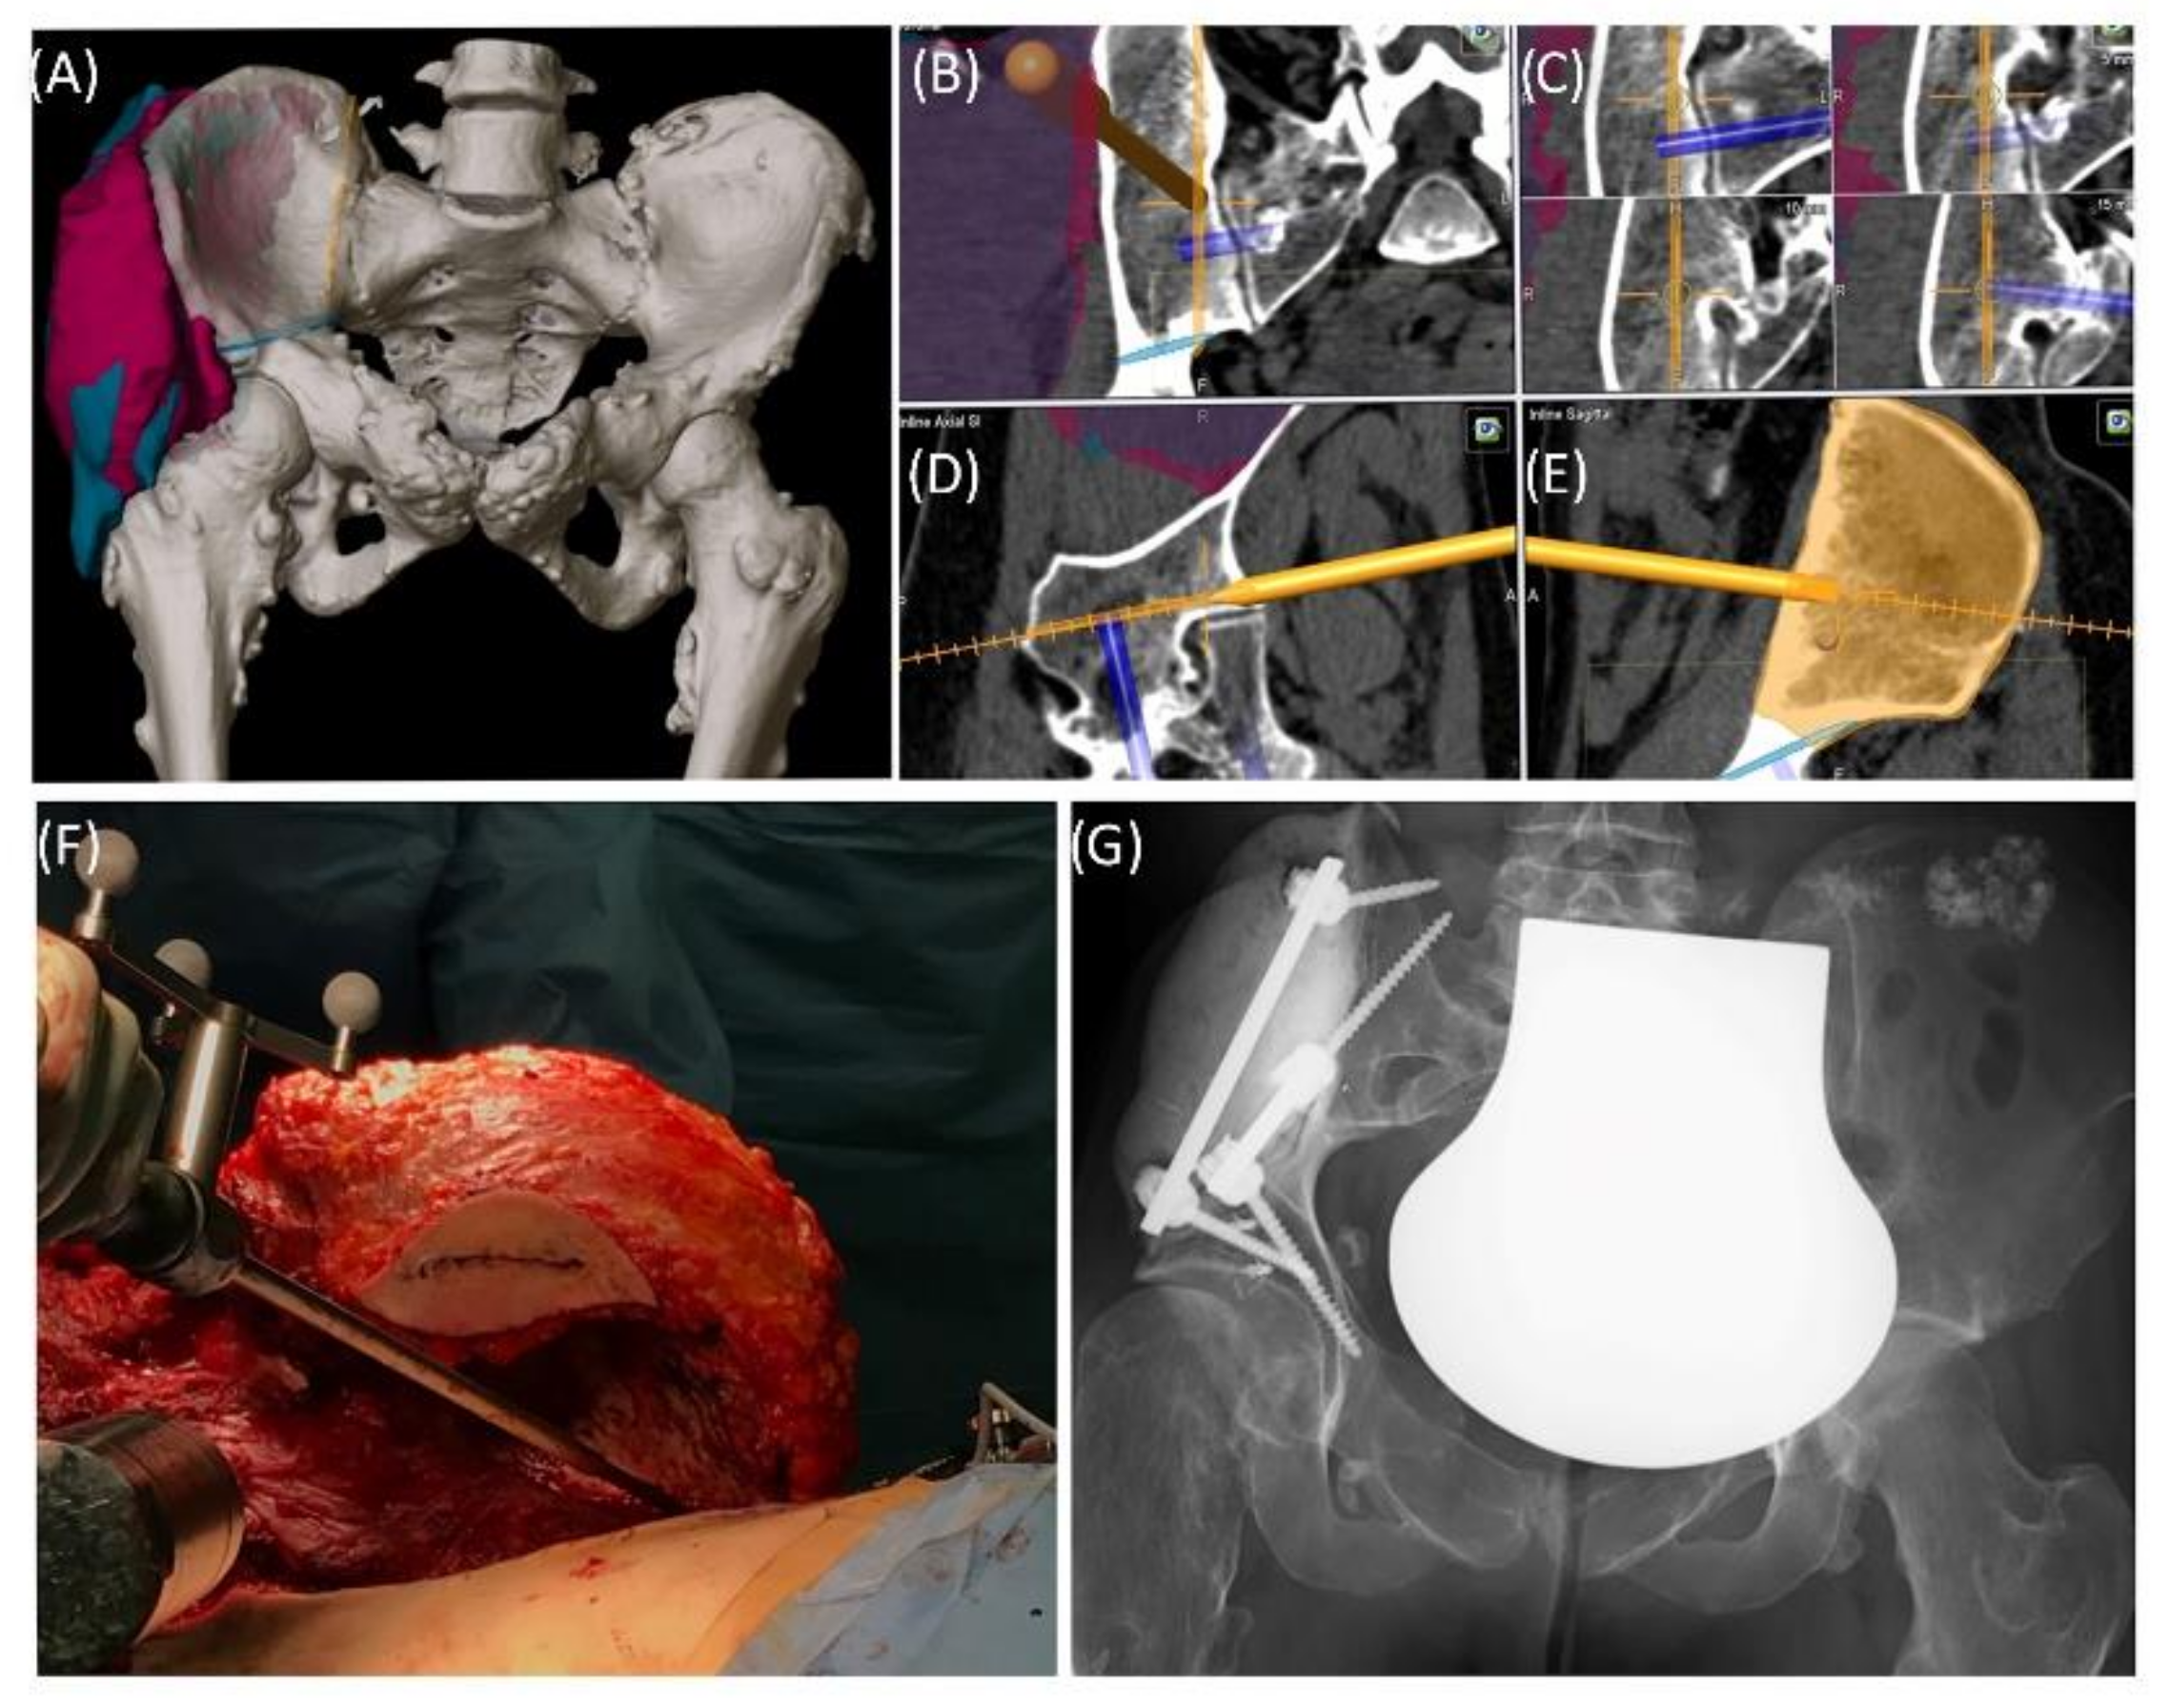

Case 1 involved a 22-year-old female patient suffering from a multiple cartilaginous exostosis disease with a secondary peripheral chondrosarcoma G3 of the right ilium without metastasis. The resection was performed as navigated internal hemipelvectomy (P1a), followed by augmentation of the right ileum with a standard screw-rod system (Expedium, DePuy Synthes Spine Inc., Raynham, MA, USA) and revision cement (COPAL® G+C, Heraeus, Wehrheim, Germany) (Figure 2). This procedure allowed preservation of the hip joint. Trochanter resection was followed by reconstruction of the ventral hip joint capsule and reinsertion of the musculature using an attachment tube (Implantcast, Buxtehude, Germany). During treatment, superficial dry skin necrosis at the Enneking approach site occurred without signs of infection and eventually healed. The first follow-up 3 months after surgery showed a stable and increasingly fluid gait pattern with a positive Trendelenburg sign. The range of motion of the right hip joint was fully preserved. At the 15-month follow-up, the patient was free of pain and was able to walk a three-kilometer distance. The native X-ray and MRI of the pelvis showed no signs of tumor recurrence.

Figure 2. Case 1: Preoperative planning and segmentation of tumor volume components [bony (pink) and soft tissue (teal)] (A); resection planes [transverse (orange) and axial (blue)] during surgery with navigated chisel (orange) (BE) intraoperative situs during resection (F); postoperative radiograph with reconstructed iliac defect (G).